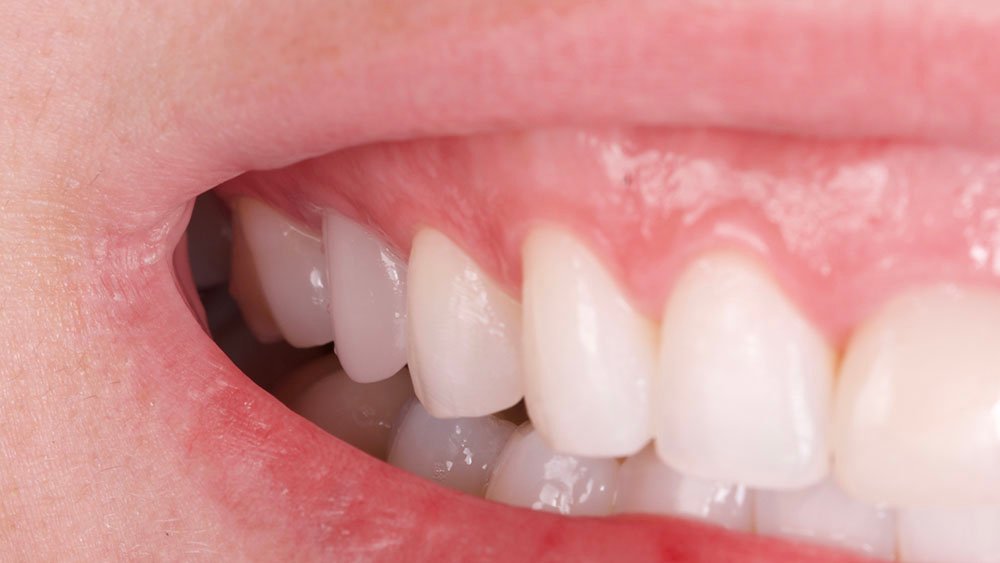

Para este relato de caso clínico selecionou-se a paciente A. S. P, do gênero feminino, de 22 anos, que procurou a Clínica de Especialização em Implantodontia devido a uma perda dentária do elemento 15 por trauma, culminando como queixa principal a ausência do elemento dental e a gengiva aprofundada.

Durante a anamnese, a paciente apresentou um bom estado de saúde geral e não relatou nenhum dado médico relevante que impossibilitasse o tratamento. No exame físico intraoral, observou uma boa condição de saúde bucal, notando-se apenas a ausência do elemento 15 com uma depressão óssea no vestibular. Dessa forma, objetivou-se um plano de tratamento baseado na utilização da técnica de rolo modificada e colocação de dente provisório.

O procedimento selecionado para esse relato de caso promoveu resultados satisfatórios e melhorou a estética. No término do procedimento cirúrgico, a paciente foi orientada a tomar uma cápsula de Amoxicilina 500 mg (EMS – Germed Farmacêutica, São Paulo- Brasil) a cada 8 horas por sete dias; um comprimido de Nimesulida 100 mg (Eurofarma Laboratórios S/A, São Paulo-Brasil) a cada 12 horas por três dias; e um comprimido de Dipirona 500 mg (Sanofi Medley Farmacêutica Ltda., São Paulo-Brasil) a cada 6 horas. Além disso, foi indicado à paciente que evitasse alimentos pastosos e pegajosos, que preferisse alimentos frios ou gelados e utilizasse bolsa de gelo no local.

No acompanhamento mensal realizou-se proservação e radiografias periapicais da região para verificar a cicatrização dos tecidos e integridade do implante. Após o período de três meses, foi cimentada uma coroa definitiva de zircônia monolítica.